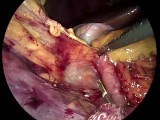

Colectomy - Laparoscopic

Sigmoid Colectomy - Colectomy

Procedure - Sigmoid

Coletcomy - Hemicoletcomy

- Laparoscopic

Sigmoidectomy Surgery - Ileostomy

Sigmoid Colon Resection - Mucous

Obstruction - Sigmoid Colon

Resection - Ulcerative